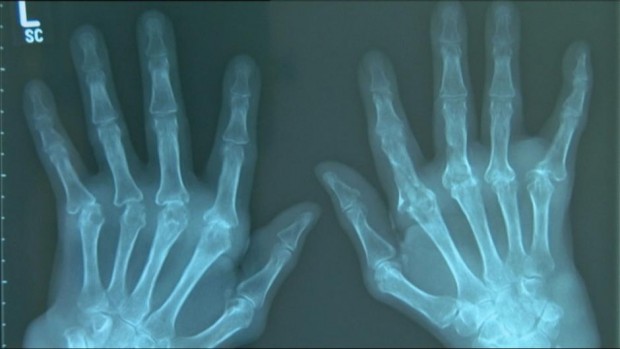

*** تشخيص هشاشة العظام: -**تشخيص حالة الإصابة بهشاشة العظام بالنسبة للأشخاص الذين يعانون من حدوث تمزق أو كسر، يعتمد علي مجموعة من الأعراض إلى جانب الاختبار البدني وأشعة إكس علي العظام.